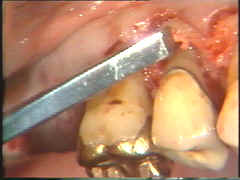

Aquí el defecto en la superficie de la raíz del central es claramente visible. Todo el tejido de granulación ha sido eliminado y el cráter óseo fué remodelado. El colgajo debe ser ubicado apilcalmente al defecto de la raíz para evitar la acumulación de placa subgingival postoperatoria.